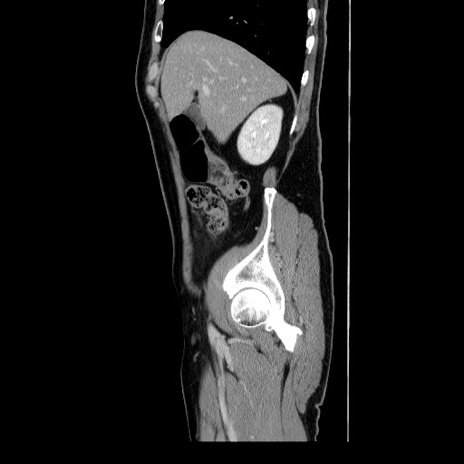

症例34(矢状断像)

【症例】60歳代 男性

【主訴】右鼠径部膨隆

【現病歴】1年程前より右鼠径部膨隆あり。自己にて還納可能だったため放置していた。3時間前より右鼠径部の脱出を認め、還納困難となり受診。

【身体所見】右鼠径部に小児頭大の膨隆あり。弾性硬であり、用手還納は困難。左鼠径部にも膨隆を認める。脱出はなし。